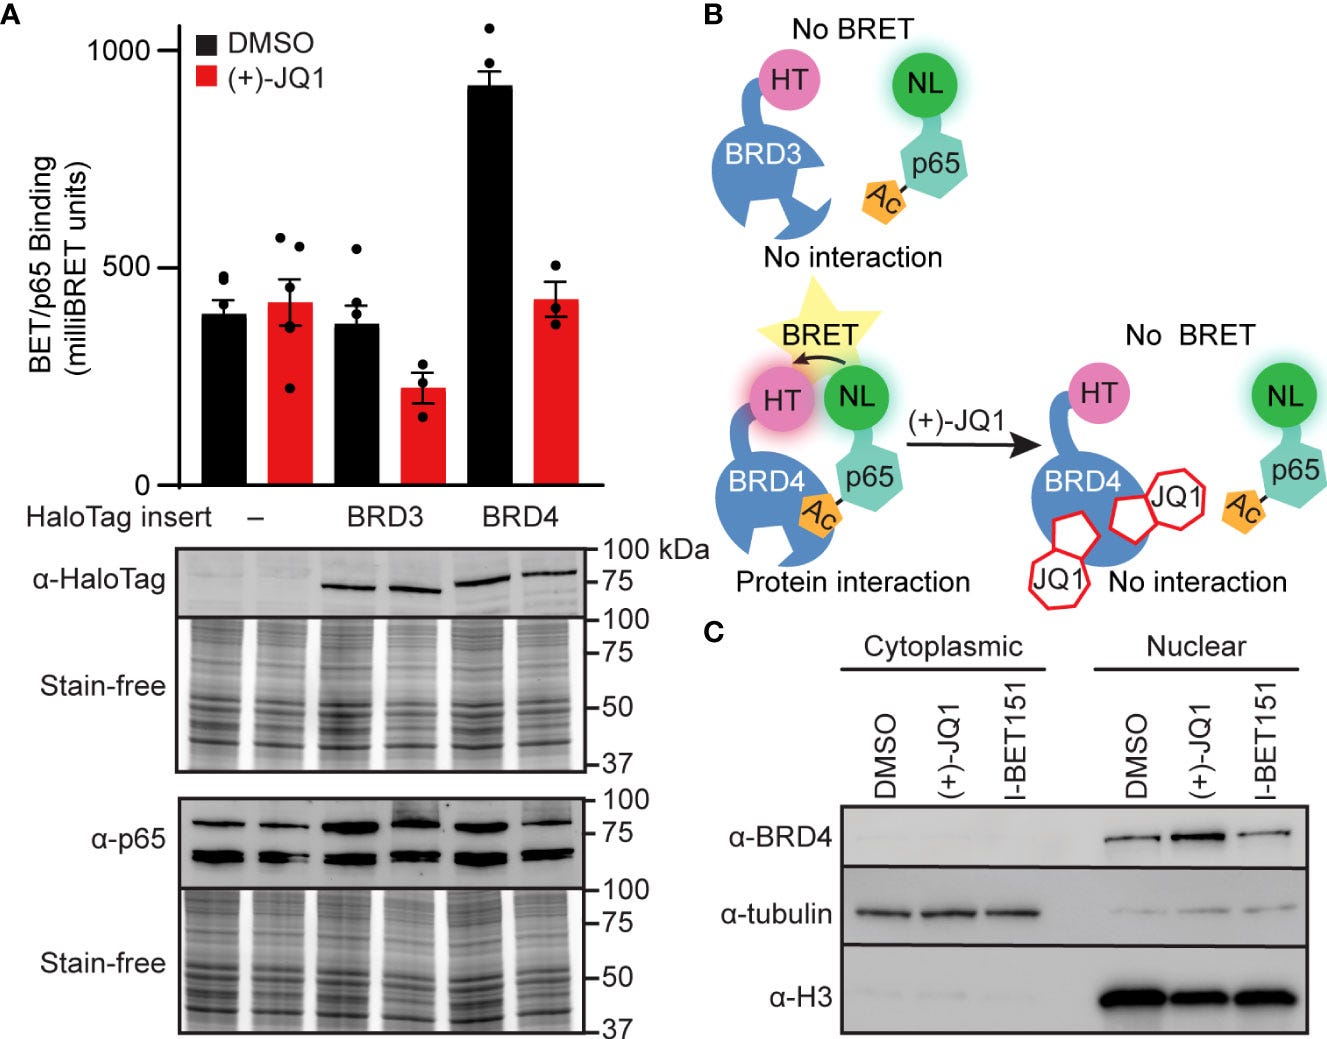

For instance, Nord et al (2022) conducted an in vitro study into how BET inhibitors can disrupt BRD4-p65 interactions and reduce inducible nitric oxide synthase transcription in pancreatic β-cells25.

They used rat insulinoma cell line INS 832/13 as these provide a useful model for studying insulin secretion regulation and pancreatic islet beta-cell function26:

Chronic inflammation of pancreatic islets is a key driver of β-cell damage that can lead to autoreactivity and the eventual onset of autoimmune diabetes (T1D). In the islet, elevated levels of proinflammatory cytokines induce the transcription of the inducible nitric oxide synthase (iNOS) gene, NOS2, ultimately resulting in increased nitric oxide (NO). Excessive or prolonged exposure to NO causes β-cell dysfunction and failure associated with defects in mitochondrial respiration. Recent studies showed that inhibition of the bromodomain and extraterminal domain (BET) family of proteins, a druggable class of epigenetic reader proteins, prevents the onset and progression of T1D in the non-obese diabetic mouse model. We hypothesized that BET proteins co-activate transcription of cytokine-induced inflammatory gene targets in β-cells and that selective, chemotherapeutic inhibition of BET bromodomains could reduce such transcription.

Here, we investigated the ability of BET bromodomain small molecule inhibitors to reduce the β-cell response to the proinflammatory cytokine interleukin 1 beta (IL-1β). BET bromodomain inhibition attenuated IL-1β-induced transcription of the inflammatory mediator NOS2 and consequent iNOS protein and NO production. Reduced NOS2 transcription is consistent with inhibition of NF-κB facilitated by disrupting the interaction of a single BET family member, BRD4, with the NF-κB subunit, p65. Using recently reported selective inhibitors of the first and second BET bromodomains, inhibition of only the first bromodomain was necessary to reduce the interaction of BRD4 with p65 in β-cells. Moreover, inhibition of the first bromodomain was sufficient to mitigate IL-1β-driven decreases in mitochondrial oxygen consumption rates and β-cell viability. By identifying a role for the interaction between BRD4 and p65 in controlling the response of β-cells to proinflammatory cytokines, we provide mechanistic information on how BET bromodomain inhibition can decrease inflammation. These studies also support the potential therapeutic application of more selective BET bromodomain inhibitors in attenuating β-cell inflammation.

This further suggests that the ability of BET inhibitors to disrupt NF-κB signaling is enacted at the point of transcriptional activation in the nucleus, rather than upstream signaling cascade components in the cytoplasm. These findings are consistent with BRD4 co-activating transcription of the NF-κB target gene NOS2 through a bromodomain-dependent interaction with p65 in the nucleus of β-cells.